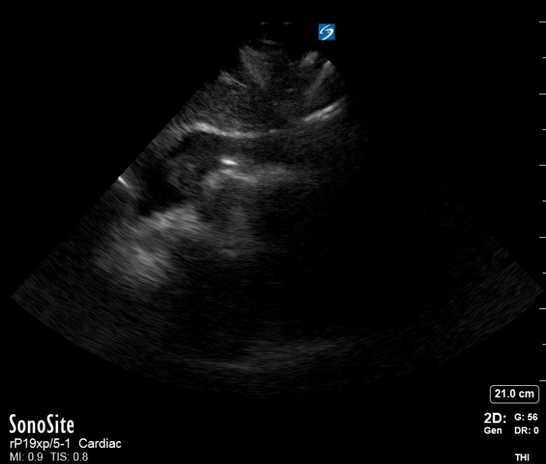

A single ultrasound view of the heart was obtained by the registrar, shown below:

On the basis of the POCUS findings, cardiothoracic surgeons were contacted and the patient was taken urgently to CT, confirming a diagnosis of Type A aortic dissection with large haemopericardium. The patient was taken to the operating theatre for repair. He went into cardiac arrest (PEA, suggesting tamponade as the cause) on arrival in the theatre and underwent sternotomy with internal cardiac massage prior to intubation. The operation then proceeded. He initially made good progress post-op and was discharged from the ICU. Unfortunately he died a week later after an unexplained cardiac arrest on the ward.

Task-fixation in POCUS manifests as a temptation to “complete the examination” or “get better views”, in this case perhaps by obtaining other standard echo windows, or even trying to visualise a dissection flap. This is dangerous because the single, limited-quality view above was sufficient to discount the possibility of ACS or massive PE and assign all clinical resources to pursuing the diagnosis of aortic dissection with tamponade; therefore, more or better views would serve only to delay definitive treatment.